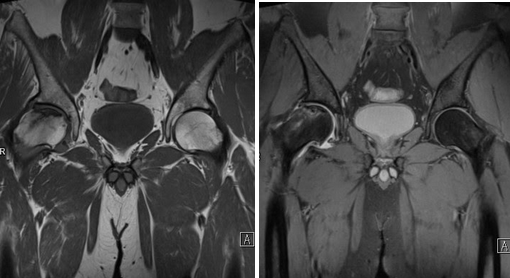

(Слева) Фронтальная Т2 МР-И: диффузный кроветворный костный мозг, вторично на фоне серповидноклеточной анемии. Серповидноклеточная анемия является фактором риска развития остеонекроза. Бедро является наиболее характерной областью поражения. Для первой стадии остеонекроза характерен отек в головке левой бедренной кости.

(Справа) Фронтальная Т1ВИ МР-И, этот же пациент, спустя семь месяцев определяется прогрессирование с коллапсом суставной поверхности: диагноз на данный момент ясен, стадия IV. Правое бедро находится в «зоне риска» или в I стадии. Согласно статистическим данным, заболевание в правом бедре разовьется в течение последующих 3-4 лет. (Слева) Аксиальная STIRMP-И, этот же пациент с серповидноклеточной анемией спустя несколько месяцев: развился классический остеонекроз в головке правой бедренной кости.

(Справа) Фронтальная Т1ВИ C+FS МР-И у пациента с переломом шейки бедра. Методы лечения включают чрескожное соединение штифтами и гемиартропла-стику. Это исследование было выполнено для оценки кровотока в головке бедренной кости. Определяется полное отсутствие усиления в головке, указывающее на посттравматическую потерю кровоснабжения и необходимость замены. (Слева) Рентгенография в ПЗ проекции: бедро после декомпрессии. Характерный неоднородный склероз при остеоне-крозеВ Декомпрессия выполнена для снижения костномозговой гипертензии и улучшения кровотока. Она также обеспечивает быстрое улучшение симптоматики.

(Справа) Фронтальная PD FSE FS МР-И: маленький очаг остеонекроза. Визуализируется след от выполненной декомпрессии. Декомпрессия лучше всего подходит для I и II стадий. При развитии перелома/коллапса изменения не обратимы.